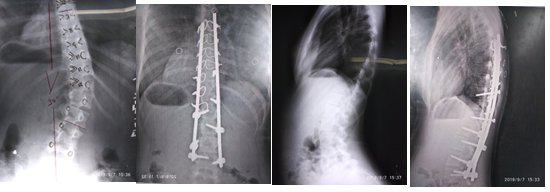

A los pacientes del grupo B se les realizó la técnica modificada por el autor de este trabajo, con una casuística de 19 pacientes. (Figura 3)

En los pacientes del grupo B, que fueron intervenidos con la técnica modificada por el autor (HPCA), la curva promedio preoperatoria fue de 56 grados y se logró una corrección del 81,9 % en el posoperatorio inmediato, con un promedio de 45,9 grados y una pérdida de 2,1 grados al año, lográndose resultados muy similares a los tornillos pediculares a full. (Tabla 6).

Se realiza un abordaje posterior de la columna vertebral, se esqueletizan apófisis espinosas, láminas, articulares y transversas a ambos lados, se liberan las partes blandas, para hacer más flexible la curva y lograr mayor corrección. Se colocan tornillos pediculares en la vértebra final inferior bilateral, en el lado cóncavo en la inmediata superior y en el lado convexo se deja una vértebra por medio. (Figura 1).

En el lado convexo, se colocan tornillos corticales de 4,5 mm a nivel del ápex de la curva. Si el ápex es una vértebra, se colocan tres tornillos uno a nivel del ápex y uno en las vértebras adyacentes superior e inferior; si el ápex es un disco, se colocan tornillos corticales en las vértebras adyacentes a este. En el lado cóncavo, en las vértebras que se les colocó tornillo cortical, se utilizan alambres sublaminares dobles de 1,2 mm. En el resto de las vértebras se colocan alambres sublaminares simples de 1,2 mm a ambos lados y dobles en la vértebra final superior. (Figura 1).

Se coloca primero la barra del lado cóncavo; se une a los tornillos pediculares y alambres, amoldada a la curva, luego se realiza la desrotación y corrección en el plano coronal y sagital. Se fijan los tornillos pediculares de ese lado y se aprietan los alambres sublaminares. Seguidamente se coloca la barra del lado convexo, por fuera de los tornillos corticales, se fijan alambres sublaminares y tornillos pediculares.

Los tornillos de corticales pueden usarse con efecto cantiléver y dan más resistencia que un alambre sublaminar, lo que aumenta la corrección y disminuye la pérdida de ésta en el tiempo.